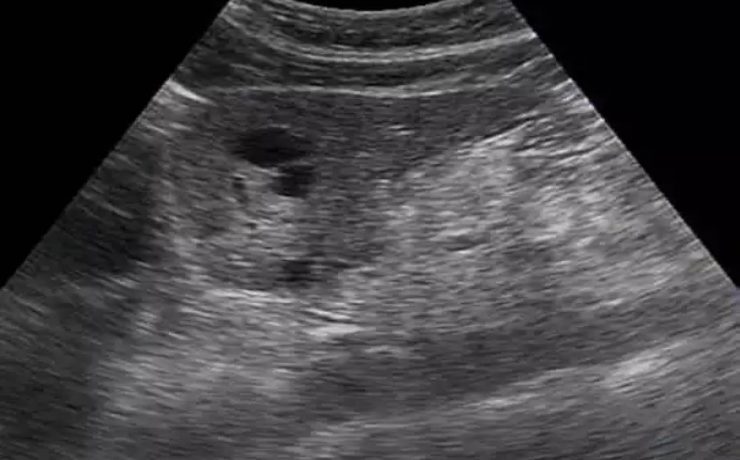

Marcadores ultrasonograficos para enfermedades genéticas

El síndrome de Down es una malformación congénita causada por una alteración del cromosoma 21 (trisomía del par 21) que se acompaña de retraso mental moderado o grave. Debe su nombre a John Langdon Haydon Down quién fue el primero que describió esta condición en 1866, Las personas con